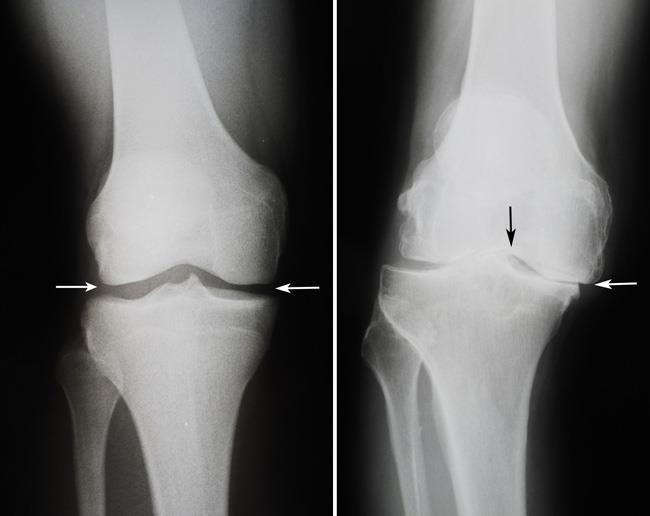

HOW YOUR XRAY LOOKS LIKE IN ARTHRITIS?

X RAY SHOWING DECREASED JOINT SPACE SUGGESTIVE OF ARTHRITIS